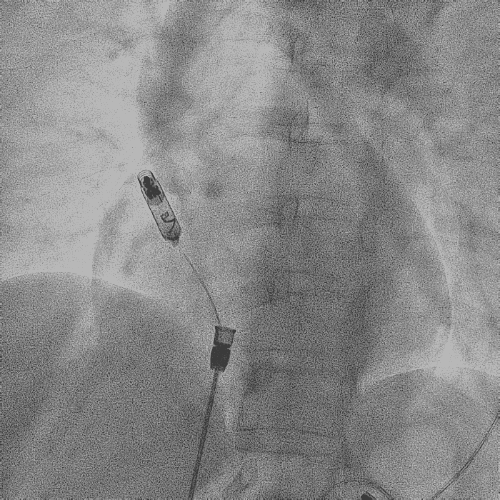

在心房和心室电极成功拔除后,患者立刻感觉“眼前一亮”,颜面肿胀感缓解,此时颈静脉怒张相比术前也明显缓解。再次复查上腔静脉造影,狭窄明显减轻,无需再使用上腔静脉扩张球囊进行扩张。

电极拔除后

颈静脉怒张

明显缓解

上腔静脉狭窄